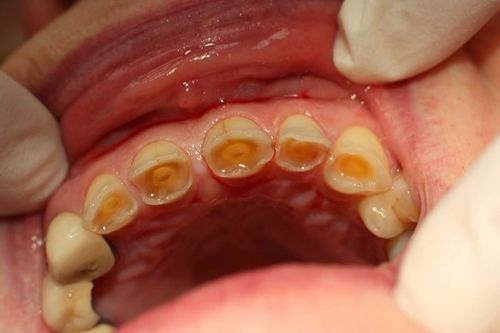

Acid trong các loại thức uống như soda, nước ngọt… là thủ phạm chính làm mòn men răng. Các loại thực phẩm có hàm lượng đường cao cũng sẽ kích thích sự phát triển của các vi khuẩn trong miệng, làm xói mòn men răng, dẫn đến tăng sự nhạy cảm ở răng.

Khi men răng bị mòn, các kích thích tố như lạnh, nóng, chua, ngọt gặp khi ăn uống sẽ làm chuyển động dịch ngà trong ống ngà dây thần kinh và gây ra chứng ê buốt. Đó là lý do nhiều người bị chứng ê răng thường phải kiêng khem những món ăn thức uống mình yêu thích.